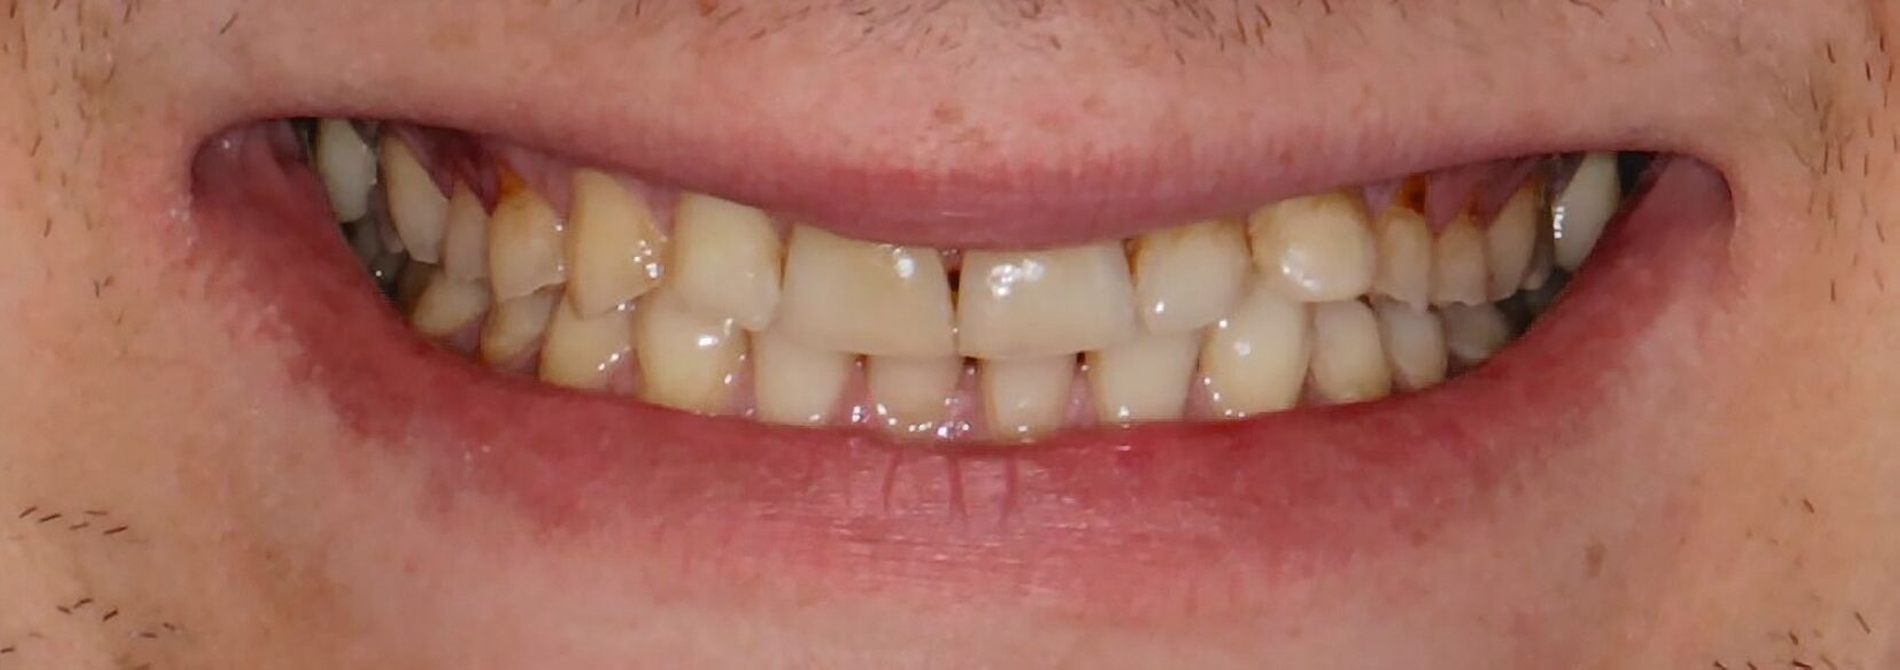

Diagnostik

Klinisch präsentierte sich ein vollbezahntes Gebiss ohne Weisheitszähne mit Defekten an der Zahnstruktur teilweise bis ins Dentin. Es waren deutliche Erosionsspuren zu erkennen, die auf die säurehaltige Ernährung im Kurzzeitintervall zurückgeführt wurden. Der BEWE-Index war mit dem Wert 13 auffällig und kategorisierte den Schaden als ausgeprägte Erosionen. Die Zähne 14, 13 und 24 wiesen nicht-kariöse zervikale Defekte auf, diese treten häufig im Zusammenhang mit Bruxismus auf [Pecie et al., 2011]. Das CMD-Screening der Deutschen Gesellschaft für Funktionsdiagnostik und -therapie (DGFDT) [DGFDT, 2024] war unauffällig, da der Patient über keinerlei Schmerzen oder Beschwerden bei Kieferbewegungen klagte. Die manuelle Strukturanalyse (MSA) nach Bumann [Fasold und Kordaß, 2012] ergab bei diesem Patienten ein myofaziales Schmerzsyndrom. Im Prämolarenbereich imponierten Zahnhartsubstanzdefekte, die Hinweise auf starkes und häufiges Zähnepressen geben. Den Patienten selbst störten seine kälteempfindlichen Zähne sowie die Gesamtästhetik aufgrund des massiven Substanzverlustes.